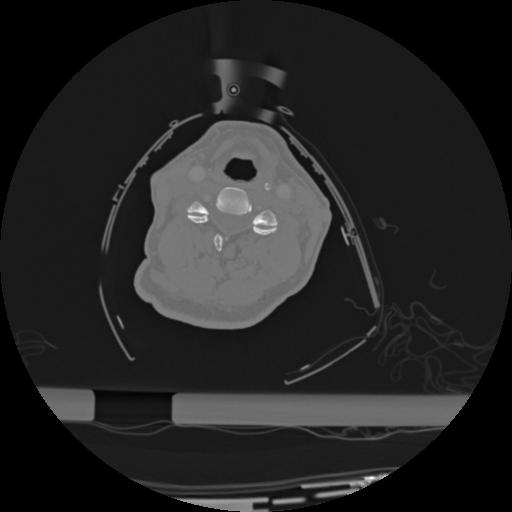

22 ANGIO,CE,Vol,0.5,ANGIO,,